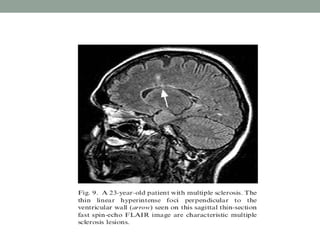

Fluid-attenuated inversion recovery

• T2-weighted imaging is well suited for lesion detection in

the brain because most lesions appear hyperintense with

this sequence.

• However CSF also appears hyperintense on T2-weighted

spin-echo (SE) images.

• Therefore, lesions at CSF interfaces, such as cortical sulci

and ventricles, may be mistaken for extensions of CSF or

partial volume effects.

• The conventional FLAIR technique employs a 180 degree

RF pulse to flip the net magnetization vector 180° and

null the signal from a particular entity (eg, water in tissue).

• When the RF pulse ceases, the spinning nuclei begin to

relax. When the net magnetization vector for water

passes the transverse plane (the null point for that tissue),

the conventional 90° pulse is applied, and the SE

sequence then continues as before.

• The interval between the 180° pulse and the 90° pulse is

the TI ( Inversion Time).

• FLAIR imaging suppresses signal from free water in CSF

and maintains hyperintense lesion contrast.

• FLAIR image have a long TR and TE and an inversion

time (TI) that is tailored to null the signal from CSF.

• FLAIR sequences are particularly useful in evaluation of

MS, infarcts, SAH